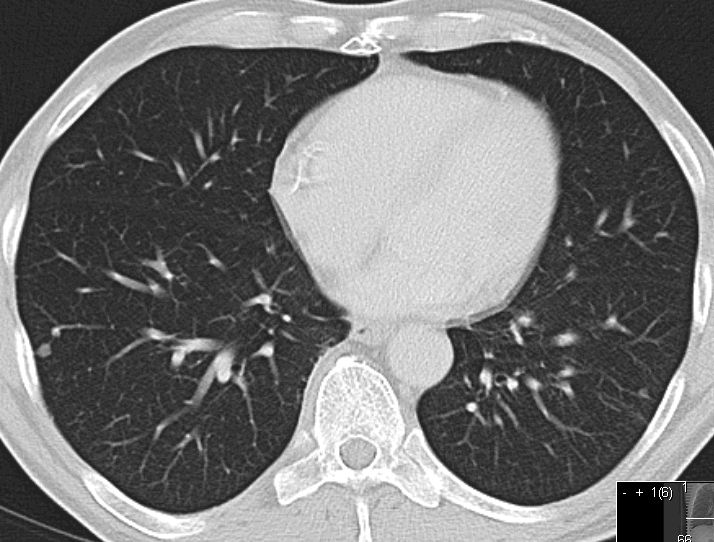

Lungenmetastasen